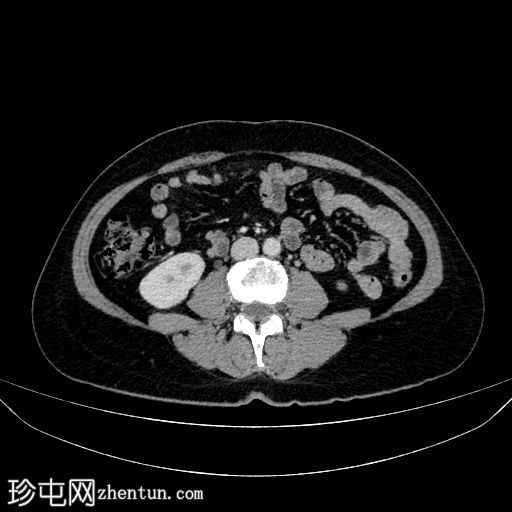

CT

轴位

平扫

轴位增强CT(门静脉期)

在这张平扫和增强CT图像中,我们可以看到右肾内有一处脂肪衰减病灶,未见并发症或其他显著异常。

肾血管平滑肌脂肪瘤是

肾脏

脂肪

性病

变最常见的病因。出血风险与血管丰富程度和瘤内动脉瘤的存在相关。本次发现为偶然发现;除非出血,否则腹痛并非肾血管平滑肌脂肪瘤的常见临床表现。